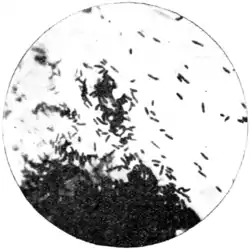

Fig. 70.—Edge of a mass of plague culture from flea's stomach. Microphotograph x 1,000.